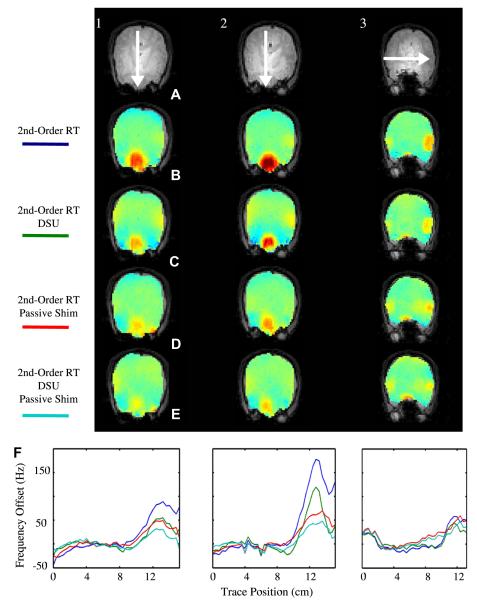

Fig. 13 illustrates significant DSU-utilized homogeneity improvement in axial slices local to the frontal sinuses and auditory cavities at B0 = 4T. Following static global shimming with up to second order shims, the global maps illustrates the severe residual inhomogeneity encountered in the frontal cortex of the brain. Field inhomogeneity of up to 150 Hz can readily be encountered a few centimeters into the brain. The field map acquired using DSU demonstrates significantly reduced frontal lobe inhomogeneity along with slight improvements near the auditory cavities. Improvements are highlighted with white arrows. These results also demonstrate that slice-specific DSU with zeroth through second-order shims cannot perfectly compensate all inhomogeneity in the human brain. The degree of improvement with DSU can also be altered with alterations in ROI definition. For instance, regions of very high inhomogeneity (such as those directly near the sinus and auditory cavities) could be omitted from slice-specific ROIs to allow the available shims to operate more selectively on lower-order inhomogeneity.

Fig. 13.

Homogeneity improvement with whole-slice optimized DSU. Field maps with (DSU) and without (global) dynamic shim changes along with slice-specific histograms for both shim settings. B0 = 4T.

5.1.2.2. EPI

As derived in Section 2.2.1, compared with conventional single-echo Cartesian imaging strategies, the phase-encoded dimension of single-shot EPI have distortion that is multiplicably exacerbated by the number of phase-encoded steps.

B0-induced distortion is often underestimated in EPI images. Distortion whereby pixels inside the brain effectively move to overlapping positions cause an intensity buildup effect that is not always easily distinguished from the underlying pixel shifts. However, this is the most common effect of image distortion. Only when pixels on the boundaries move in such a way so as to distort the outer shape of the brain is distortion obvious to the naked eye.

Such distortion is significant in high-field EPI images at typical imaging bandwidths (100–250 kHz). Using Eq. (28a), the displacement in the phase-encode direction of a given pixel can be related to the measured B0 offset at that pixel. For a 64 × 64 in-plane acquisition with a readout bandwidth of 100 kHz, an image shift of one pixel occurs in the phase-encoding direction for 24.5 Hz of B0 offset. Thus, one could effectively replace the color contrast limits in Fig. 13 with ±6 pixels to uncover how far each pixel will move in the phase-encode direction of an EPI acquisition.

Fig. 15 demonstrates improvement in geometric distortion comparing EPI images with a static global shim and second-order DSU. Improvement in the EPI images depends on slice position. The middle slices show limited improvement due to their initial (global second-order RT shim) lack of significant inhomogeneity. A number of slices show signal recovery and reduced image distortion (as indicated with yellow arrows). However, while DSU does make significant improvements, it is clear that the resulting EPI images still contain residual artifacts.

Fig. 15.

EPI images (64 × 64 in-plane pixels over 25.6 cm × 25.6 cm, 4 mm slices, B0 = 4T, TR = 2500 ms, TE = 25 ms, and readout bandwidth of 100 kHz) under static and dynamic second-order shim settings for axial slices (from left to right). Dotted lines indicate the brain contours as extracted from an undistorted FLASH acquisition (top row). Arrows designate areas of significant image quality improvement.